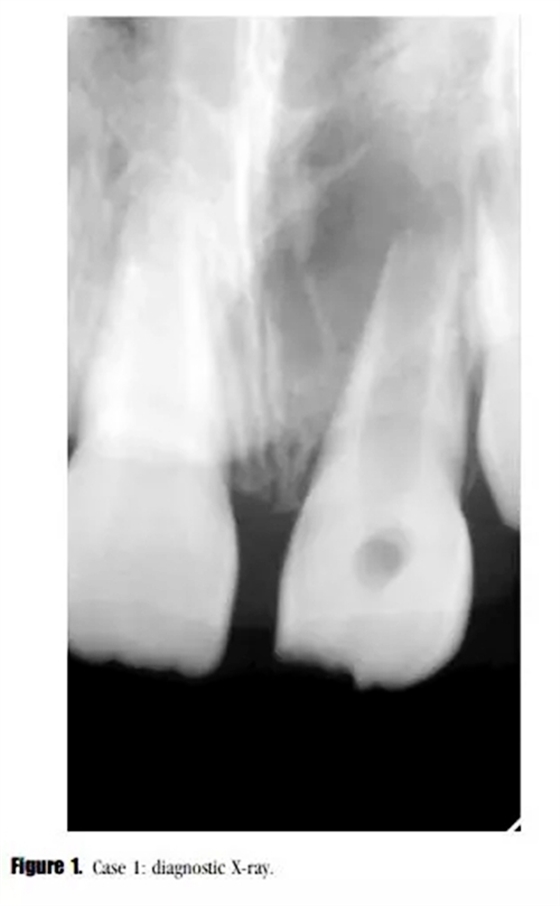

主訴:左上恒中切牙腫脹。(圖1)

影像學檢查: X線顯示,21根尖發(fā)育達到第三階段,根尖區(qū)被大面積低密度透射影像包繞?;佳辣辉\斷為慢性根尖周炎急性發(fā)作。

在3,6,9個月的隨后跟蹤隨訪中,患者完全沒有癥狀。與鄰牙和對側(cè)牙對比,21的叩診、捫診以及牙周袋深度都在正常范圍內(nèi)。對于牙髓溫度測試沒有反應。影像學評估顯示,根尖區(qū)低密度透射影像范圍減小,牙根發(fā)育為I型(按照Chueh等人的研究)(圖2),